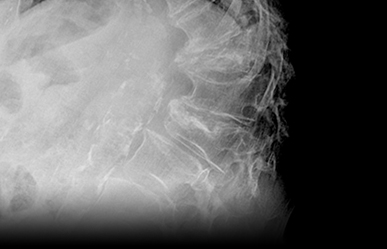

If a VCF or other serious condition is suspected, the next step is usually to get imaging of your back. This may include x-rays, CT scan and or MRI.